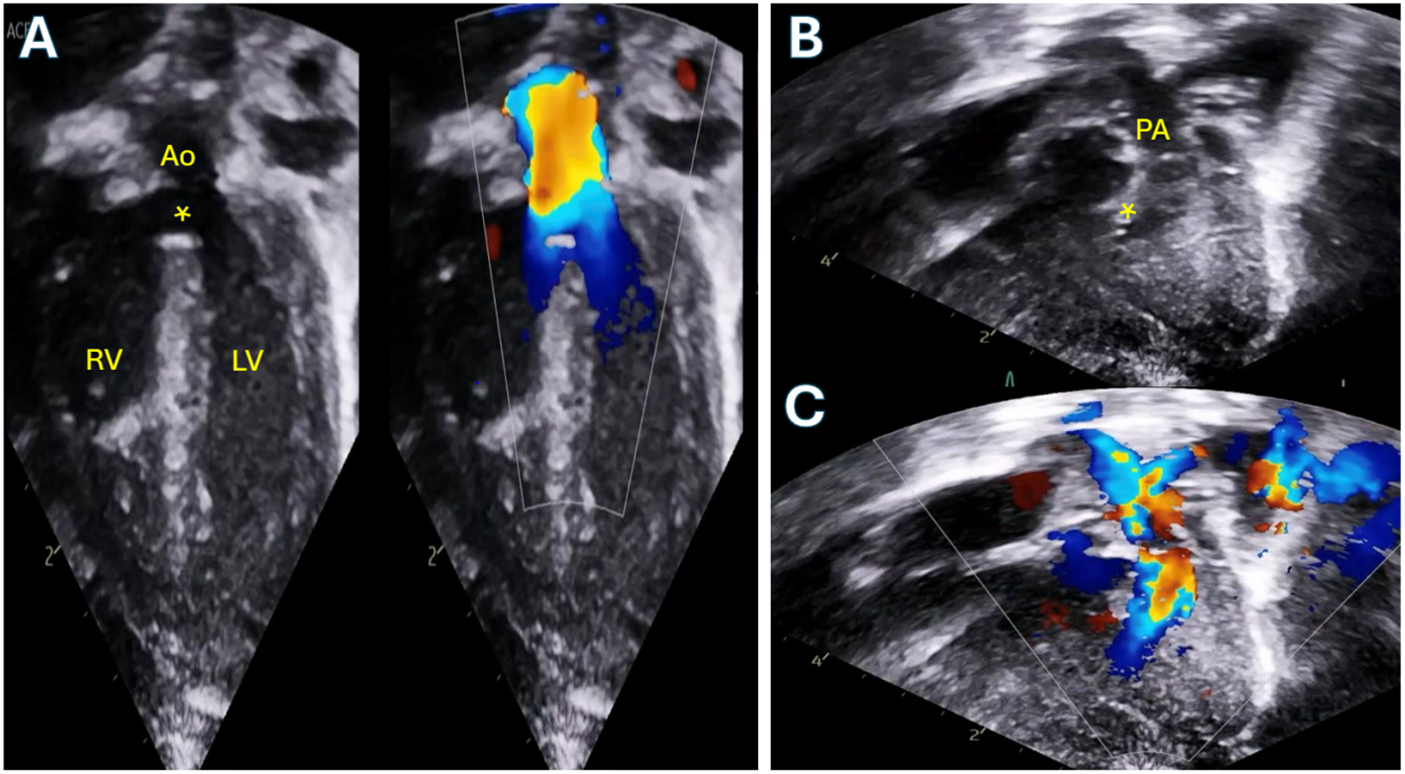

Figure 1: Transthoracic echocardiogram of a neonate with Tetralogy of Fallot with moderate pulmonary valve stenosis. A: Apical 5-chamber view demonstrating the large ventricular septal defect (asterisk) and overriding aorta. B: 2D modified subcostal view demonstrating the anteriorly deviated conal septum with sub-pulmonary crowding. C: Color Doppler of the same view demonstrating flow acceleration beginning below the level of the pulmonary valve. RV: Right ventricle; LV: Left ventricle; PA: Pulmonary artery